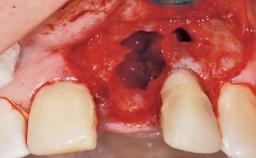

A 39-year-old male patient presented with a chief complaint of discomfort and gingival discoloration around his maxillary left central incisor. He was in good general health and was a non-smoker. His past dental history was significant because of the traumatic fracture of tooth 21 in a sporting accident at age 13. Initial dental treatment included endodontic therapy and a full-coverage restoration. The patient became symptomatic 5 years later, when structural failure of the tooth resulted in the dislodgment of the crown. Endodontic retreatment, apical surgery, and post-and-core restoration were performed.